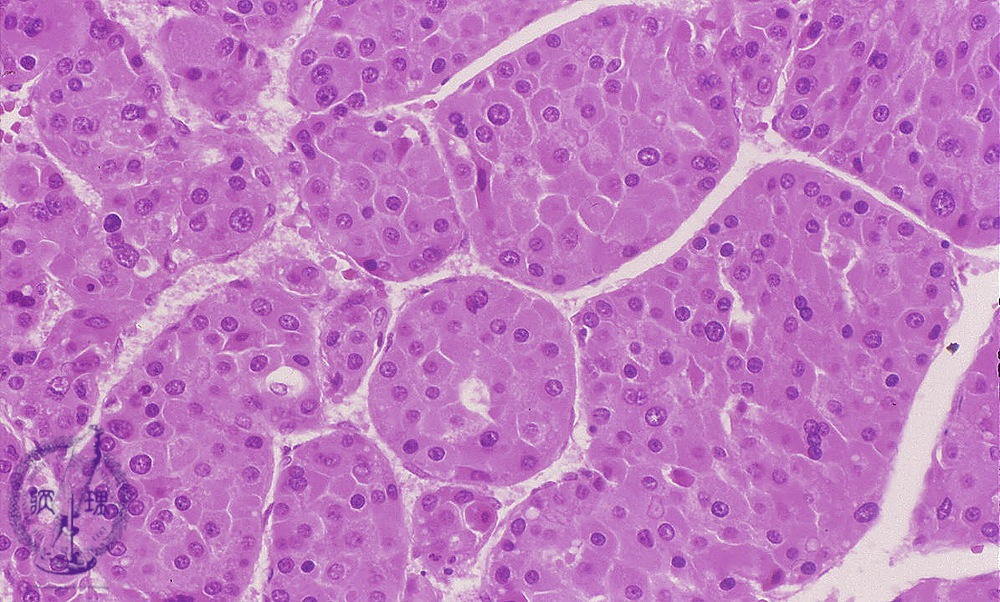

• š(12)Hepatocellular carcinoma

Microscopic finding (HE stain, high power view): Classical hepatocellular carcinoma with trabecular pattern resembling hepatocytes. Vascular channels separate and surround the individual tumor trabeculae.